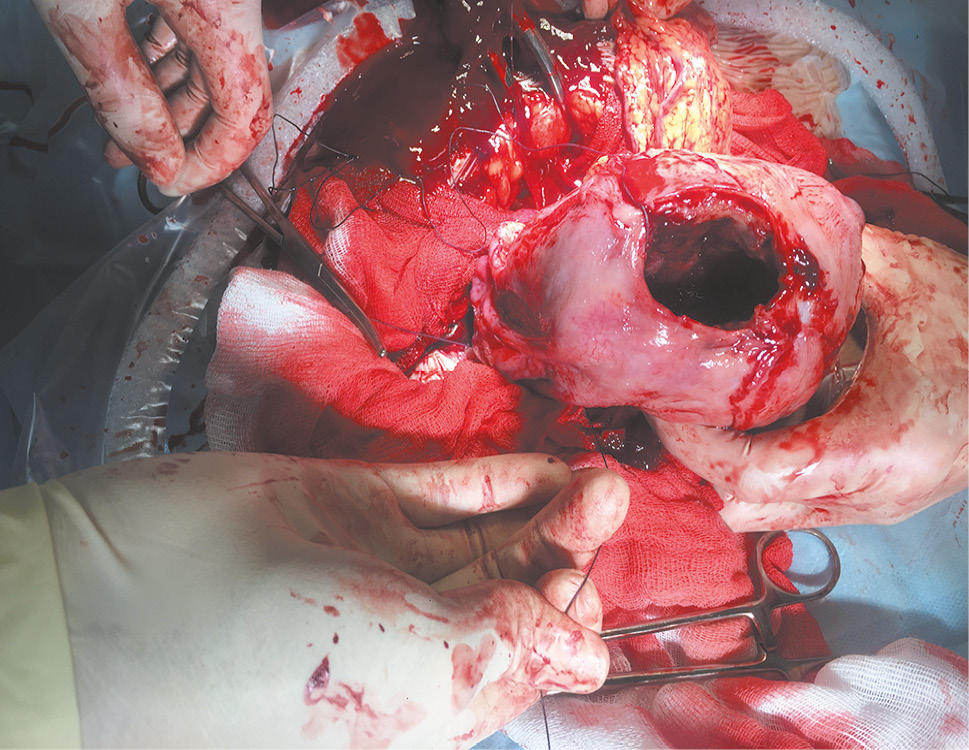

During the case follow-up (within 4 h), the intensity of labor did not increase, and there was no positive dynamics in the birth canal. The diagnosis of primary uterine inertia was established. Delivery by cesarean section was proposed to the patient. After obtaining consent, antibiotic prophylaxis with cefazolin at a dose of 1.0 g was administered intravenously 30 min before surgery. A Pfannenstiel laparotomy was performed, followed by cesarean section in the lower uterine segment. A live full-term boy weighing 3,800 g was extracted with an Apgar score of 8 and 9 points. The placenta was located along the front wall of the uterus, 7 cm above the internal os, separated by moderate traction of the umbilical cord, and the retained products were 22 × 22 × 1.5 cm in size. The lower segment was represented by connective tissue, thinned to 0.2 cm, and was not deformed. When performing exteriorization, a complete rupture of the uterus of a rounded shape with a size of 5 × 4 cm was revealed in the uterine fundus (see Figure). A rupture in the uterine fundus after excision of the edges was sutured with a continuous three-row suture using a polyglycolide thread. Scar tissue of the lower segment was excised; the incision on the uterus was closed with a double-row continuous suture using a polyglycolide thread. Hemostasis was achieved. The abdominal cavity was drained using an active drainage in the left iliac region. The laparotomy incision was closed in layers. Blood loss during the surgery amounted to 800 ml. The postoperative diagnosis included surgical delivery at a term of 39–40 weeks; incompetent uterine scar; primary uterine inertia; complete uterine rupture; Pfannenstiel laparotomy; cesarean section in the lower uterine segment; suturing the rupture of the uterine fundus; abdominal drainage.

Intraoperative observation of complete fundal rupture of the uterus at the first stage of labor

Интраоперационная картина полного разрыва дна матки в первом периоде родов